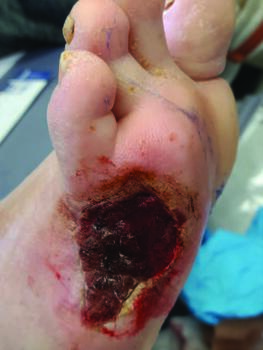

More recently, the term chronic limb threatening ischemia (CLTI), has emerged as a more appropriate term that more accurately reflects the varying degrees of ischemia in patients with diabetes that can delay or prevent wound healing. In addition, it accounts for the non-critical nature of limb ischemia, whereby revascularization is not urgently needed for limb preservation, and it addresses the fact that amputation is not based solely on the severity of ischemia, but also on the wound characteristics, including presence of infection (see photo on left above).14,15